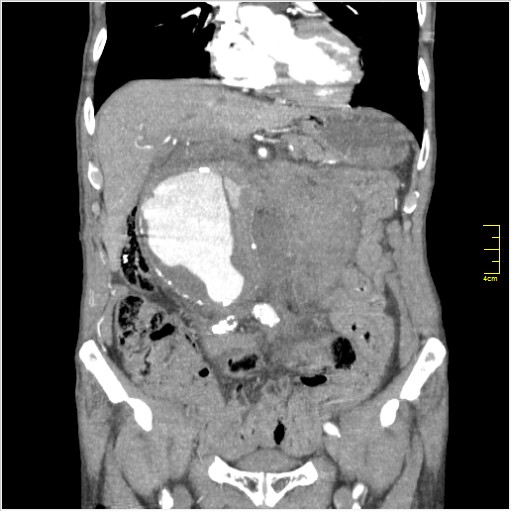

КТ брюшной полости. Мужчина с пальпируемой опухолью в животе

Пациент Т. 64 года, обратился на КТ брюшной полости амбулаторно (!), по направлению семейного врача с диагнозом abdominal mass, буквально: образование брюшной полости.

ИМХО простые кисты.Uzgraph писал(а):Случай интересный - ногу сломишь. Вроде бы анефризма брюшной аорты(особенно по УЗИ), но что тогда за образования сидят на левой почке - онкология?

Huge abdominal aorta aneurism. Simple renal cortical cysts (Bosniak type 1).